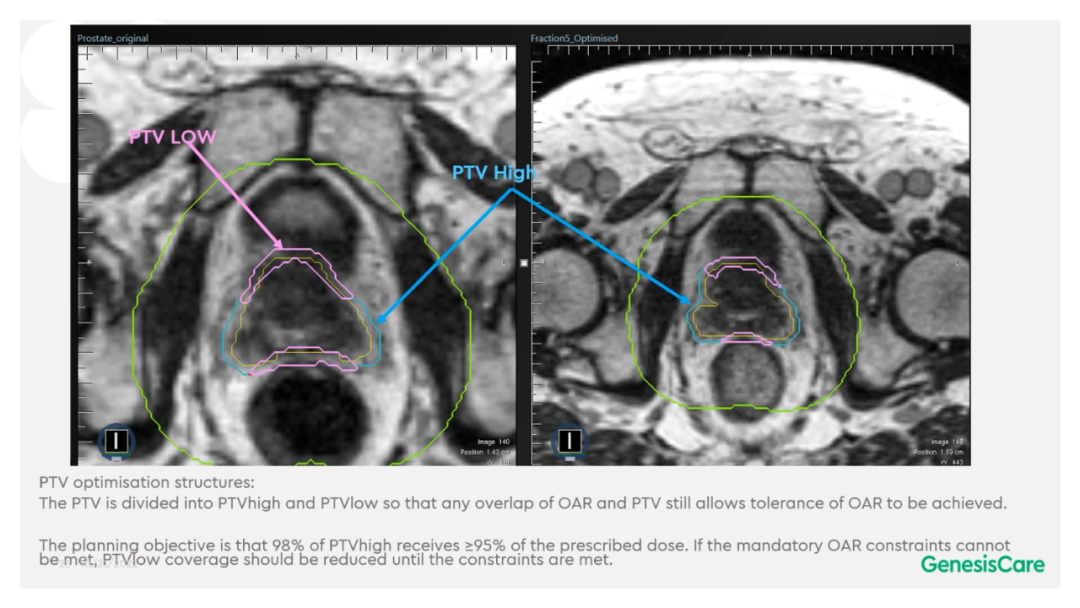

Dr. CamilleriÌåÏÖ£¬£¬£¬£¬£¬£¬£¬ËûÃÇÔÚ×öÔÚÏß×Ô˳Ӧ·ÅÁƵÄʱ¼ä£¬£¬£¬£¬£¬£¬£¬ÎªÁËÌá¸ßËÙÂÊ£¬£¬£¬£¬£¬£¬£¬½ö¶Ô°ÐÇøÍâ·Å3cmÒÔÄÚµÄΣ¼°Æ÷¹ÙµÄת±ä¾ÙÐÐ×Ô˳Ӧµ÷½â»òÖØÐ¹´»ÂÖÀª£¬£¬£¬£¬£¬£¬£¬¼ûFigure 13¡£¡£¡£¡£¡£¡£ÕâÑù¿ÉÒÔËõ¶ÌÂÖÀª¹´»µÄʱ¼ä¡£¡£¡£¡£¡£¡£¹ØÓÚ·ÅÁÆÍýÏ룬£¬£¬£¬£¬£¬£¬Ê¹µÃ95%µÄ°ÐÇøÌå»ý½ÓÊܵ½100%µÄ´¦·½¼ÁÁ¿ÁýÕÖ£¬£¬£¬£¬£¬£¬£¬²¢½«×î´ó¼ÁÁ¿ÏÞÖÆÎª2%µÄ°ÐÇøÌå»ý²»Áè¼Ý´¦·½¼ÁÁ¿µÄ110%£¬£¬£¬£¬£¬£¬£¬ÕâÑù¾ÍÄܰü¹ÜÔÚͼÏñÉϺÜÄÑÏÔʾµÄÄòµÀ²»»á³¬Á¿£¬£¬£¬£¬£¬£¬£¬¼ûFigure 14¡£¡£¡£¡£¡£¡£ÁíÍ⣬£¬£¬£¬£¬£¬£¬ÔÚÖÆ×÷·ÅÁÆÍýÏëʱ£¬£¬£¬£¬£¬£¬£¬½«PTV·ÖΪPTV LOWºÍPTV High£¬£¬£¬£¬£¬£¬£¬PTVºÍΣ¼°Æ÷¹ÙÖØµþµÄ²¿·ÖΪPTV LOW£¬£¬£¬£¬£¬£¬£¬½«PTV LOWµÄ¼ÁÁ¿Ä¿µÄÉ趨ÔÚΣ¼°Æ÷¹ÙµÄÄÍÊܼÁÁ¿ÒÔÏ£¬£¬£¬£¬£¬£¬£¬ÕâÑù¾ÍÄܰü¹ÜΣ¼°Æ÷¹Ù²»³¬Á¿£¬£¬£¬£¬£¬£¬£¬¼ûFigure 15¡£¡£¡£¡£¡£¡£